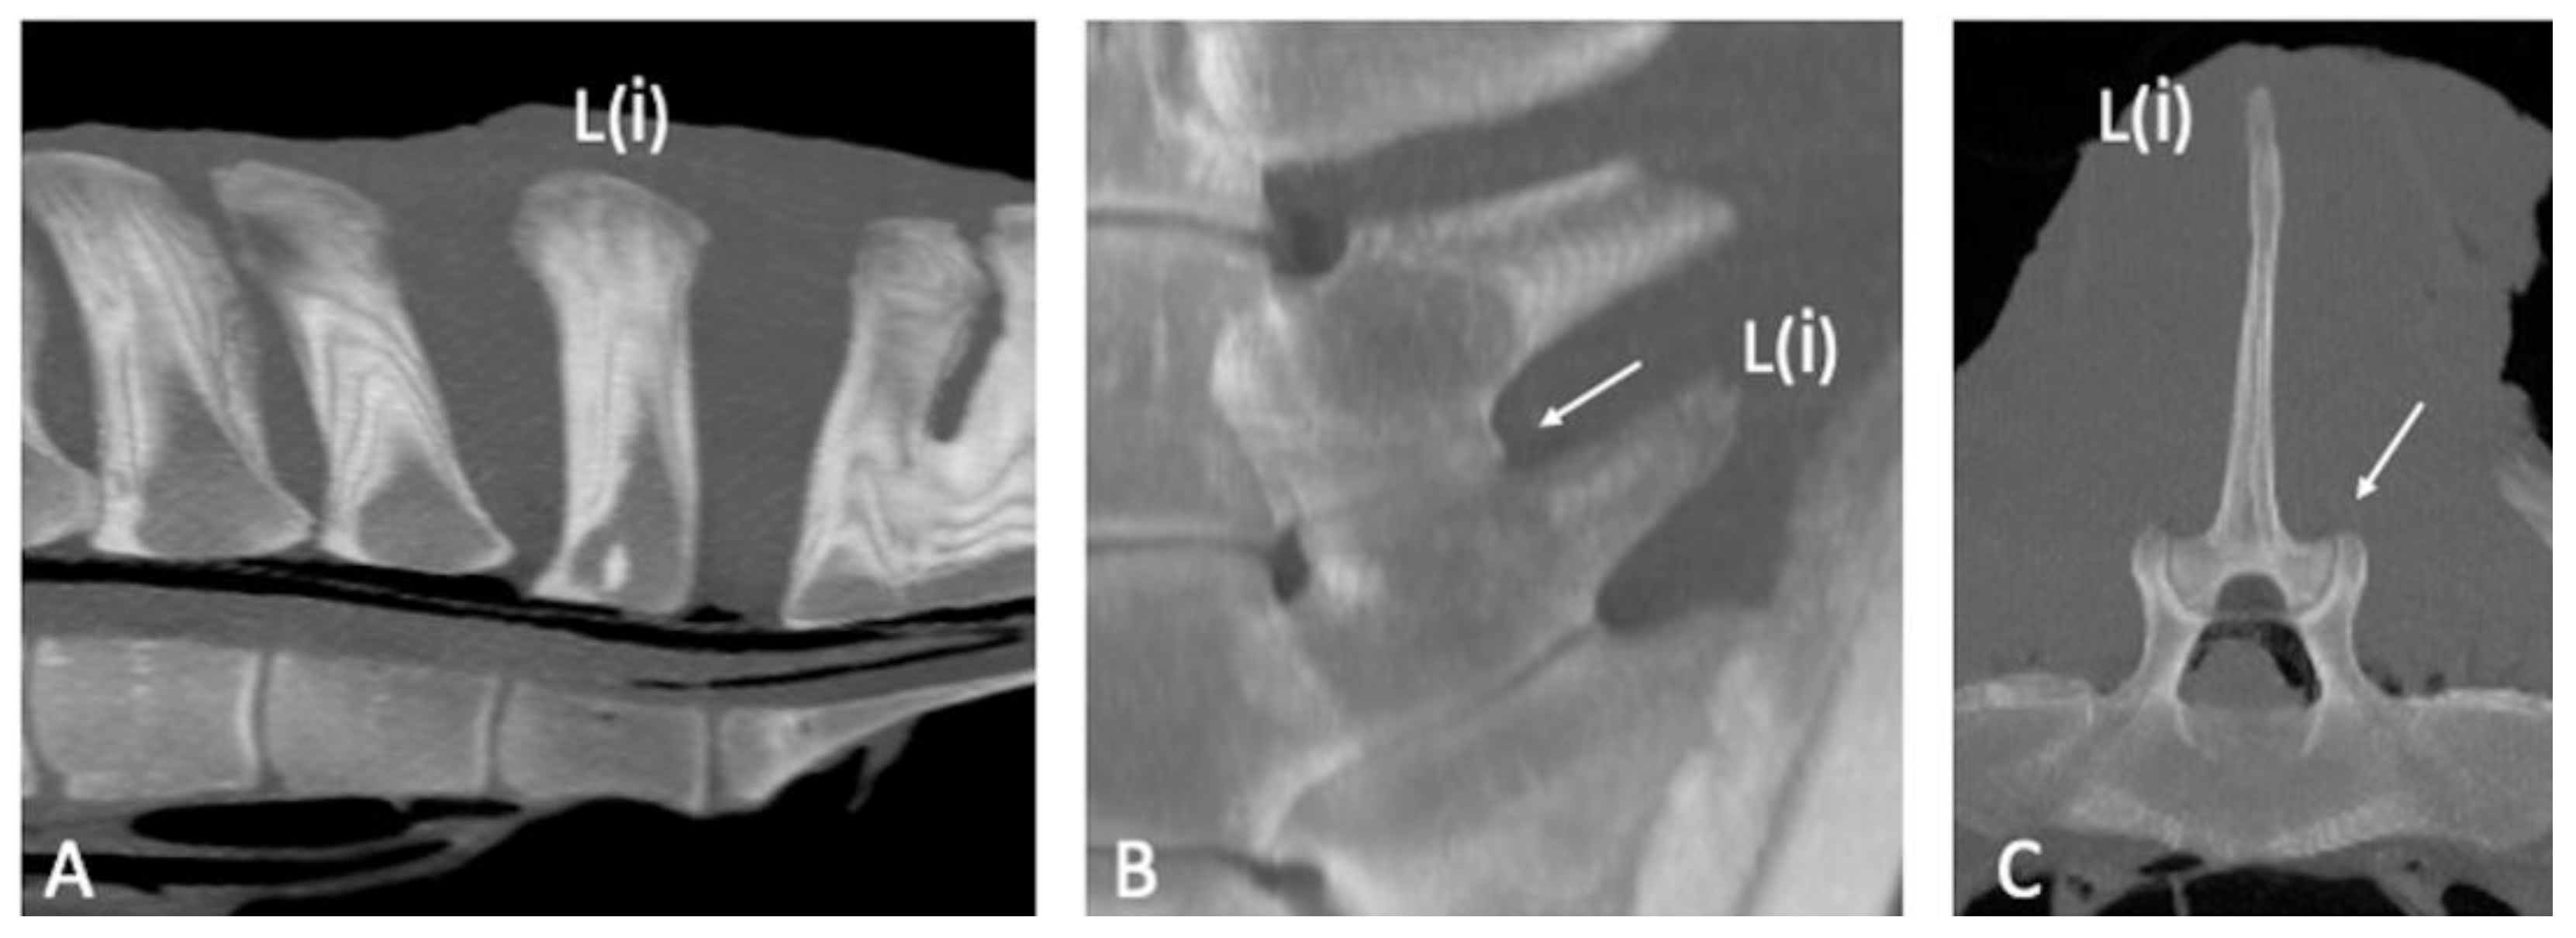

The CT appearance of two specimens without abnormalities [6] was characterized by homogeneous bone density (HU) of the bony structures (SPs, APJs, ITJs, and vertebral bodies). Differences in bone density between cortical (>1000 HU) and trabecular bone (>300 HU) of the vertebral structures were observed [19]. The periarticular bone margins were regular, and well-defined joint spaces were detected (Figure 1).

Figure 1. Sagittal ((A); cranial is toward the left), dorsal ((B); cranial is toward the top) and transverse ((C); dorsal is toward the top) multiplanar reconstruction computed tomographic images of the lumbar specimen 5, using maximum intensity projection. (A) Presence of visible intervertebral space and absence of spondylosis, spondylolisthesis and lumbar spinous processes contact or fusion. Note the spinous process (SP) of L(i) perpendicular to the orientation of the column axis, mild irregularity of the bone surface of the L(ii) SP onto the dorsocranial aspect and contact between the S1 and S2 SPs and moderate irregularity of the dorsocaudal aspect of the S1 SP and dorsocranial aspect of the S2 SP; fusion of the ventral portion and part of the middle portion of the S1-S2 SPs (B,C) Regularity of the articular margins and the joint space of the L(ii)-L(i) intertransverse joint and L(ii)-L(i) articular processes joint (arrow); the L(ii)-L(i) intertransverse space is mildly narrowed on the abaxial aspect. L(i): the most caudal lumbar vertebra.